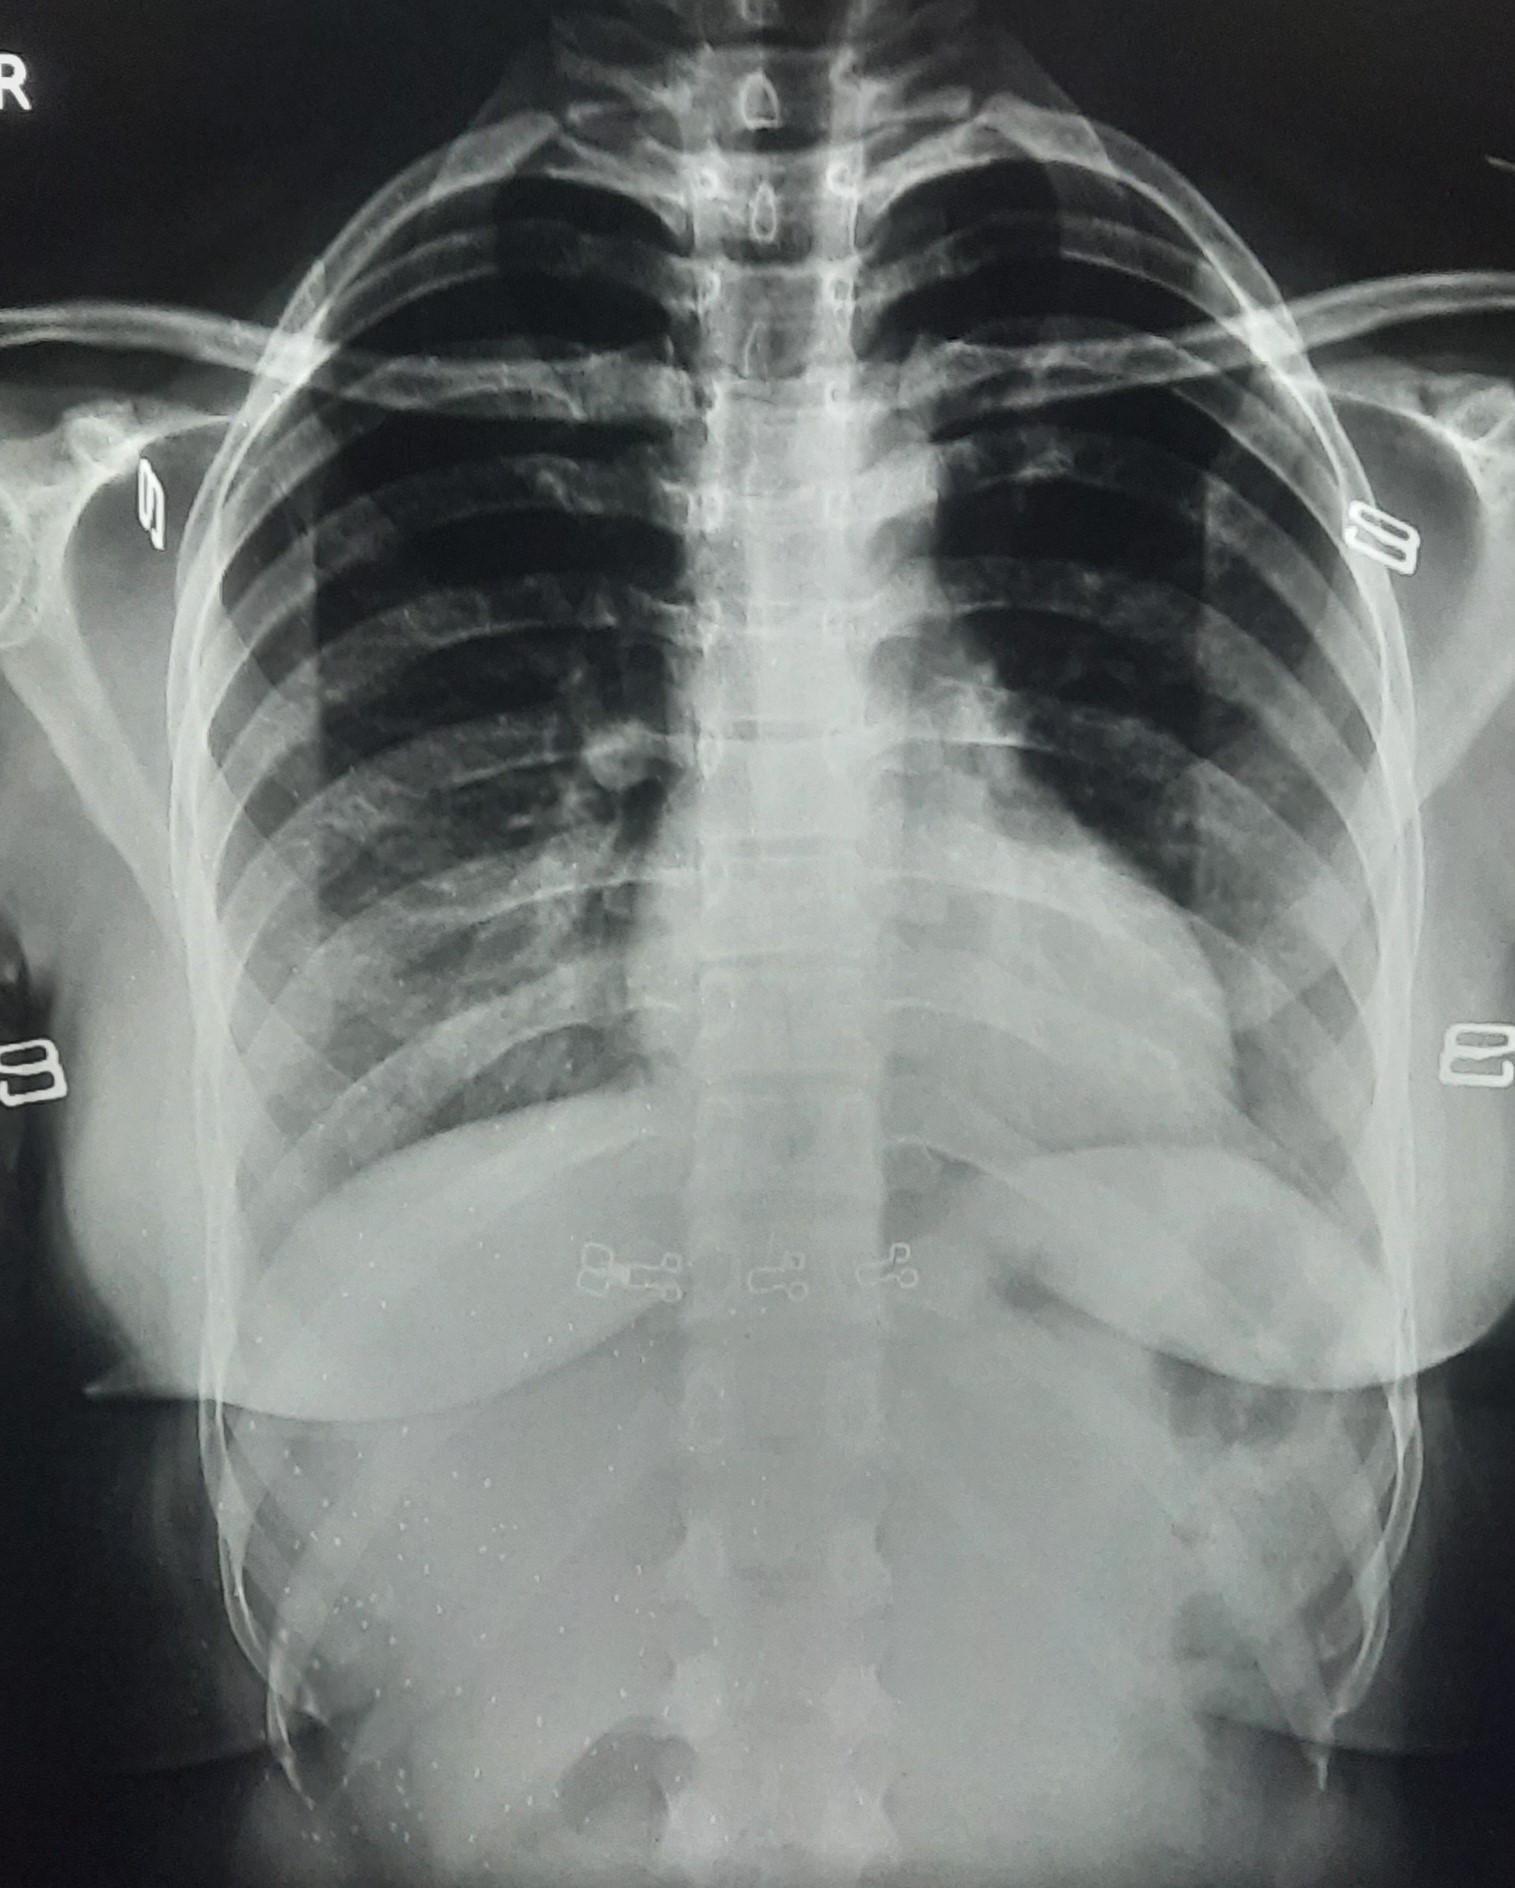

| 338 | IGGMC, Nagpur, Nagpur | P2 | 29-4134 | Rupesh Dongse | Consent taken on Paper | 43 Yrs. |

Provisional Diag : Consolidation

Final Diag : Bilateral Consolidation Community Acquired Pneumonia With Type 1 Respi Failure In Cronic Alcoholic |

Non-TB Case (Confirmed) | Bilateral Consolidation | Abnormality visible on x-ray |